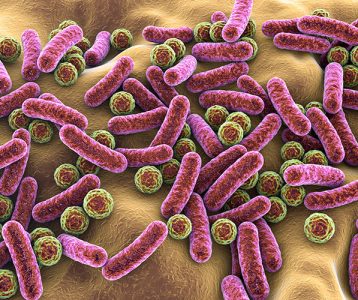

Dados da literatura sugerem que o risco de câncer colorretal está fortemente associado a fatores de estilo de vida, incluindo um componente dietético que pode ser mediado pela microbiota intestinal. Estudos recentes demonstraram, ainda, que a microbiota do cólon é alterada em pacientes com a neoplasia. Além disso, já foi comprovado que bactérias probióticas específicas modulam a inflamação e reduzem a proliferação tumoral em modelos animais de carcinogênese e podem oferecer benefícios terapêuticos para pacientes com a doença.

Para comprovar os achados, pesquisadores norte-americanos realizaram um estudo clínico visando investigar a composição da microbiota de pacientes com câncer de cólon – em comparação com controles sem a doença neoplásica ou inflamatória. Além disso, avaliaram o potencial de probióticos para modificar a microbiota do cólon. O estudo envolveu a análise de amostras de biópsia obtidas da mucosa e do tumor durante a colonoscopia de 15 pacientes com a neoplasia. Amostras subsequentes foram colhidas na cirurgia do tumor e da mucosa próxima.

A microbiota tumoral foi caracterizada pelo aumento da diversidade microbiana e enriquecimento de vários táxons, incluindo Fusobacterium, Selenomonas e Peptostreptococcus – em comparação com a microbiota do grupo controle. “Pacientes com câncer de cólon que receberam probióticos tiveram uma maior abundância de bactérias produtoras de butirato, especialmente Faecalibacterium e Clostridiales spp no tumor, mucosa não tumoral e microbiota fecal”, relatam os autores. Ao mesmo tempo, os gêneros associados à neoplasia, como Fusobacterium e Peptostreptococcus, tendiam a ser reduzidos na microbiota fecal de pacientes que receberam os probióticos.

De acordo com os autores, pacientes com câncer de cólon abrigam uma assinatura de microbiota distinta no tecido tumoral e na mucosa próxima, que foi alterada com a intervenção probiótica. “Como a microbiota associada ao câncer colorretal está sendo continuamente definida à medida que novos biomarcadores da doença são descobertos, a disbiose microbiana observada em pacientes pode ser manipulada por bactérias probióticas”, acentuam.